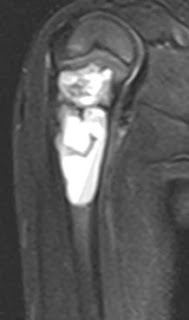

T1 and STIR coronal and sagittal MR images in a 4 year old child showing a fairly well demarcated expansile septate cystic lesion in the proximal metaphyseal region of right humerus. It displays mild heterogeneity but is largely homogenous.

SIMPLE BONE CYST:

-90% occur in long bones, most common in proximal humerus

-Metaphyseal expansile cystic lesion

-May contain "fallen fragment" which is a fractured fragment of bone which moves in dependent part with change in patient position. It is usually seen on x-rays and CT.

-May show fluid-fluid level on CT and MRI